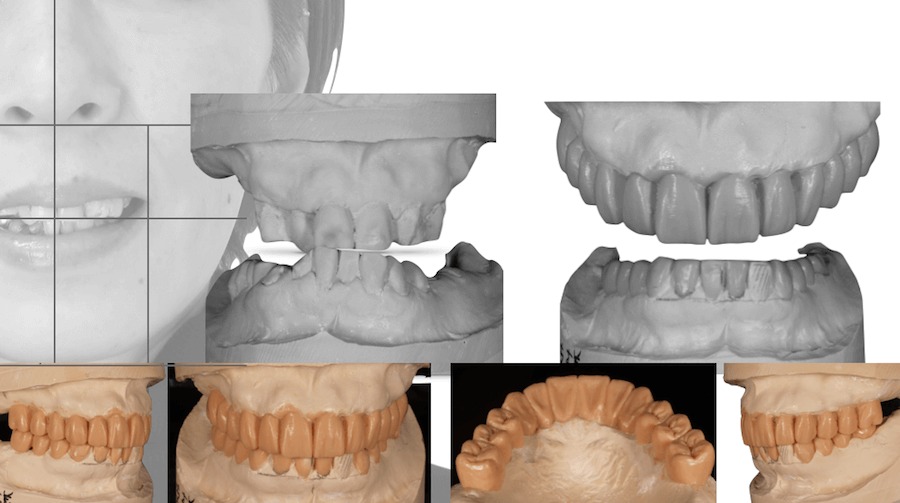

3Dシミュレーション

Nobel Clinicianによるインプラント埋入の為の3Dシミュレーション

Nobel Clinician®︎という、インプラント診断様用のソフトを用いて正確にインプラントを入れる位置を決定する。

その後送られてくるサージカルテンプレートを用いて、インプラントを埋入する